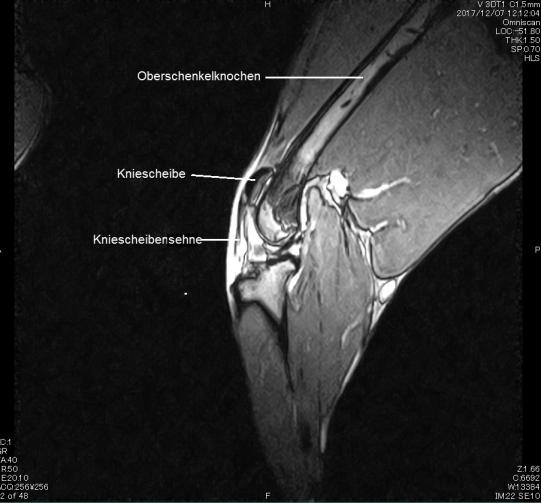

Gleichentags wird Adlin in Narkose gelegt und das Knie mittels Magnetresonanz-Tomografie (MRT) untersucht. Glücklicherweise zeigt sich, dass die Sehne nicht komplett gerissen, sondern nur stark überdehnt ist. Der Hund erhält einen Verband mit einer Schiene, welche das Knie in einer etwas gestreckten Position fixiert, um so die Sehne zu entlasten.

Für die Funktion des Hinterbeines ist die Sehne von zentraler Bedeutung: Sie überträgt die Kraft des grossen Oberschenkelmuskels (Quadriceps) via der "Umlenkrolle" Kniescheibe an den Schienbeinkopf und erlaubt so die Streckung des Knies. Reisst die Sehne, so ist der Hund nicht mehr in die Lage, über das Bein Kraft auszuüben, wodurch es funktionslos wird. In diesem Fall ist die chirurgische Reparatur des Risses zwingend.